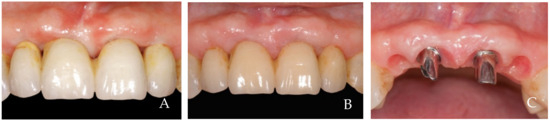

2. Clinical Examples of Oral Soft Tissue Growth